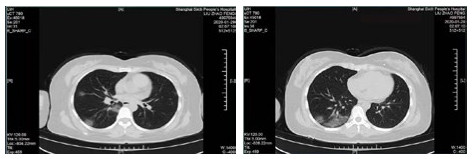

| 图 5 患者,女性,44岁,沪籍,发病前10 d内有与确诊NCP患者接触史。出现发热,体温38.5℃,乏力,伴肌肉酸痛,既往体健。血白细胞总数及淋巴计数正常,甲型、乙型流感筛查阴性,新型冠状病毒核酸检测阳性。肺部CT提示双肺多发磨玻璃结节,病灶贴近胸膜伴支气管充气征及病变内血管充血、增粗 Fig 5 Case 5, female, 44 years old, born in Shanghai, had contact history with NCP patients within 10 days before the onset of the disease. Her body temperature was 38.5℃, with fatigue, muscle ache, previous physical fitness. Normal WBC and lymphoid count, negative influenza A and B virus screening, and positive novel coronavirus nucleic acid test. Lung CT showed multiple ground glass nodules in both lungs. The lesions were close to the pleura with bronchiectasis and congestion and thickening of blood vessels in the lesions |

| 图 6 患者,女性,55岁,既往体健,沪籍,无明确武汉流行病学接触史。发热6 d,伴咳嗽,体温39.4℃,伴肌肉酸痛,流感病毒A型IgM阳性,抗柯萨奇病毒IgM阳性,新型冠状病毒核酸检测阴性。肺部CT提示双肺散在磨玻璃结节,部分贴近胸膜。诊断甲型流感病毒性肺炎 Fig 6 Case 6, female, 55 years old, born in Shanghai, was physically healthy, and had no clear history of epidemic exposure of Wuhan. She had fever for 6 days, body temperature was 39.4 ℃, with cough, muscle ache, positive influenza A IgM and anti Coxsackie IgM, negative novel coronavirus nucleic acid test. Lung CT showed ground glass nodules were scattered in bilateral lungs, some of which were close to pleura. She was diagnosed as influenza A virus pneumonia |